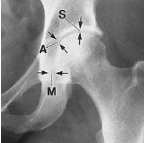

Q what is the name of this measurement? and what is the average + range?

A: Acetabular Depth

assesses the depth of the acetabulum. The average is 13 mm for males (range 7-18 mm) and 12 mm for females (range 9-18 mm).

A: Centre-Edge Angle

assesses the coverage of the femoral head by the acetabulum. The average is 36°, with a range of 20-40°.